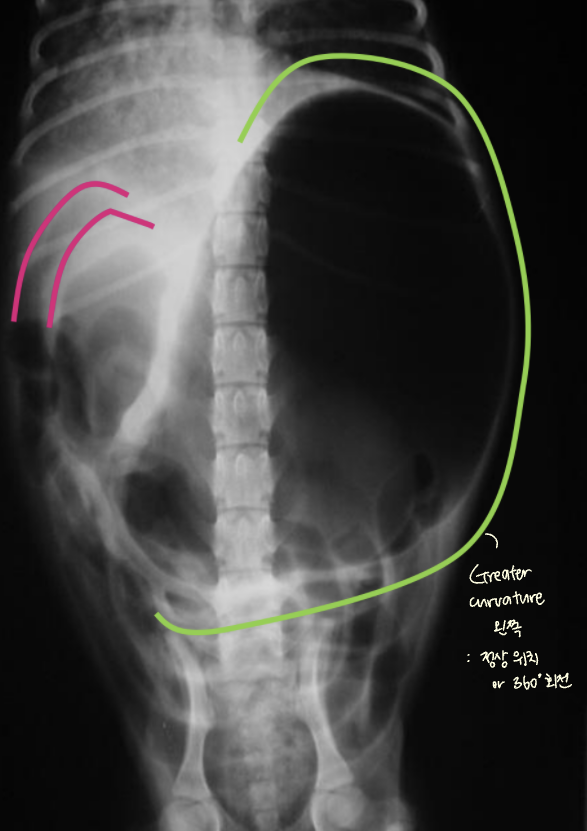

| GD | GDV | |

| VD | - greater curvature ์ผ์ชฝ(์ ์) * 360๋ ํ์ ์์๋ ์ผ์ชฝ์ ์์น | - greater curvature ์ค๋ฅธ์ชฝ (180๋ ์ผ์ ) - duodenum ์์น๋ ํจ๊ป ๊ผฌ์ |

| RL | - pylorus๊ฐ ์๋์ชฝ(์ ์) | - pylorus ์์ชฝ - ์์ ๋ถํํ(compartmentalization) : ๋ถ๋ฐฉ ํ์ธ - gastric band (soft tissue) ๊ด์ฐฐ |

![]() ![]() | ![]() ![]() | |